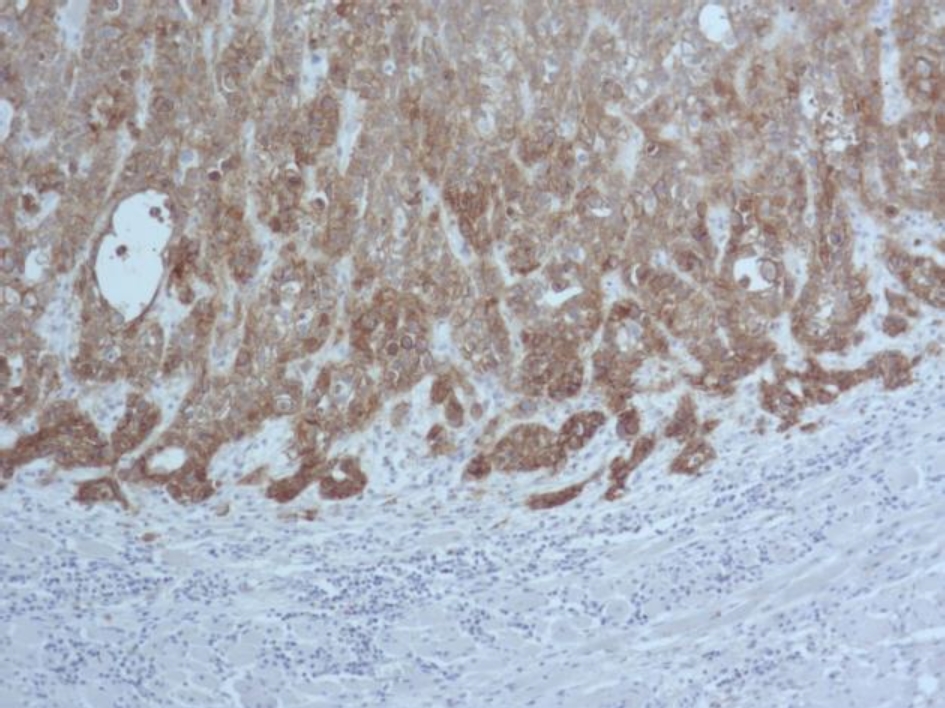

Во всех 19 исследуемых наблюдениях проведено дополнительное параллельное иммуногистохимическое исследование по выявлению экспрессии белков EGFR и Cyclin D1 соответственно, при этом диффузная, преимущественно умеренная экспрессия EGFR опреде-лялась в 17 (89 %) из 19 наблюдений (рис. 3), очаговая слабая экспрессия – в двух наблюдениях (11 %).

Рис. 3. Диффузная экспрессия EGFR в клетках плоскоклеточного рака языка. ИГХ окрашивание, ×100

В нашем исследовании в 100 % наблюдений с амплификацией гена EGFR выявлена экспрессия белка EGFR, однако в 89 % экспрессия была сильной, а в 11 % наблюдений – умеренной. Исследователями также в 100 % наблюдений рака языка выявлено соответствие между амплификацией гена EGFR и экспрессией белка EGFR, однако наблюдения с высоким количеством копий EGFR сопровождались более интенсивной экспрессией белка EGFR при иммуногистохимическом исследовании. Мы не выявили такой закономерности.